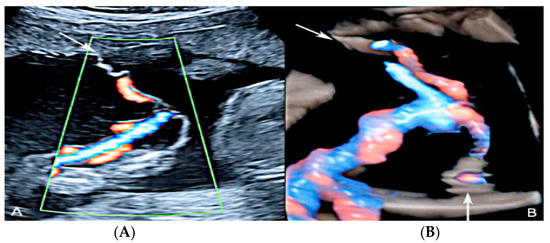

3.2.2. Vasa Praevia